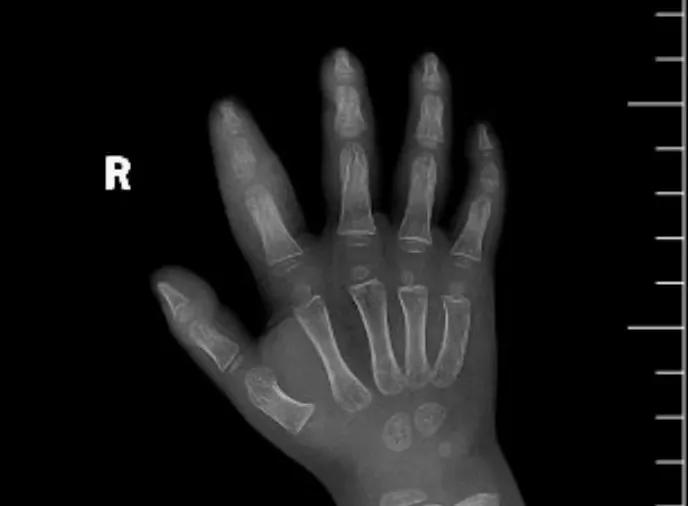

近日,市二院顯微外科接診一名3歲半的小患者,被玉米葉割傷右食指,因家長疏忽大意,導(dǎo)致一個小小的傷口竟然發(fā)展成了骨髓炎。來院時患兒右食指腫脹明顯,既不能伸也不能彎,皮膚發(fā)燙,疼得哇哇大哭。

第三天開始,月月哭鬧不止,一直說手疼,怎么哄也不行,于是在當(dāng)?shù)蒯t(yī)院治療了10來天,然而月月的手指依然腫得像個胡蘿卜,疼痛感依然存在。此時,月月的媽媽才覺得事情不大對勁,于是經(jīng)過打聽,慕名來到市二院顯微外科。入院后,經(jīng)檢查發(fā)現(xiàn),月月的右食指骨質(zhì)有侵蝕,骨骺有缺損,甚至?xí)绊懸院笫种傅陌l(fā)育。聽到這個消息,月月媽媽感覺心都揪住了。

隨后,經(jīng)顯微外科團隊充分的討論,制定了科學(xué)細致的治療方案,為月月做了感染灶清除及手指的開放引流,并留取了標(biāo)本做細菌培養(yǎng),為進一步的合理用藥提供依據(jù)。經(jīng)過兩周的治療,月月的手指終于順利消腫愈合,并且手指功能活動良好。說起這一個多月的煎熬,月月媽媽不禁落淚,但總算是治愈了,笑容又重新回到她們一家的臉上。